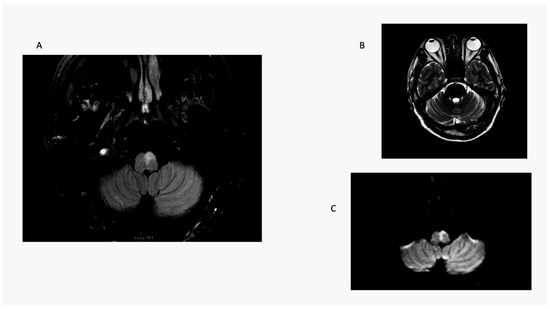

| 1 R OLD 52 | RE: 32.2 LE: 32.2 Hypometric saccades | R lateral medulla, cerebellar tonsil, uvula, and nodulus. | H direction changing | Normal | No | Noted at 32 h exam; present 6 weeks later. Resolved between 6 weeks and 5 months | Ataxia grade 3 to right |

| 2 R OLD 75 | RE: 21.9; LE 22.4. Hypometric saccades | R lateral medulla and lateral cerebellum. | H second degree to L | Normal | Ocular tilt reaction | Noted at 30 h exam; present during hospital stay for 3 days. | Ataxia grade 3 to right |

| 5. R OLD 41 | RE: 34.9; LE 25 Hypometric saccades | False-negative in initial MRI. Second MRI: stroke R lateral medulla. | Primary gaze h LBN. Did not follow Alexander’s Law | Normal | Yes | Noted at first exam and at 12 h. Resolved in 48 h. | Ataxia grade 3 to right |

| 6. L OLD 49 F | RE: 21.4; LE: 36.2 Hypometric saccades | False-negative in initial MRI. Second MRI: L lateral medulla. | H 1st-degree RBN | Normal | Yes | Not checked at first visit; present at 36 h exam; lost to f/u. | Ataxia grade 2 to left |

| 7. R OLD 62 F | RE: 13.6; L:0.1 Hypometric Saccade | False-negative in initial MRI. Second MRI: stroke R lateral medulla. | H LBN second degree | Normal | yes | OL Noted at 24 h exam, resolved in 12 h. | Ataxia grade 3 to right |

| 8 R OLD 63 M | RE: 29.3; LE: 27.35 | R lateral medulla. | Second-degree torsional to L shoulder/h-RBN | Normal | OTR | Noted at 32 h exam. | Ataxia grade 3 to right |

| 9 R OLD 51 M | RE: 35.6; LE 26.6 | False-negative in initial MRI. Second MRI: stroke R lateral medulla. | UBN | Normal | yes | Noted at 48 h exam. | Ataxia grade 3 to right |

| 10 R OLD 59 M | RE: 45.3, LE: 42.3 | R dorsolateral medulla. | Bilateral h gaze-evoked nystagmus | Normal | Yes | OLD at 6 h | Ataxia grade 2 to right |

| 11 R OLD 28 M | RE: 35.6, LE: 20.9 | R lateral medulla and cerebellum. | H LBN torsional top pole to left shoulder. | Normal | No | OLD at 24 h. | Ataxia grade 3 to right |

| 12 L OLD 39 M | RE: 22.4, L: 18/1 | L lateral medulla and cerebellum. | H RBN in center fixation, h-gaze-evoked nystagmus. | Normal | No | OLD at 24 h. | Ataxia grade 3 to left |

| 13. R OLD 45 M | RE:40, LE: 34.4 | R lateral medulla. | No nystagmus. | Normal | No | OLD at 6 h. | Ataxia grade 3 to right |